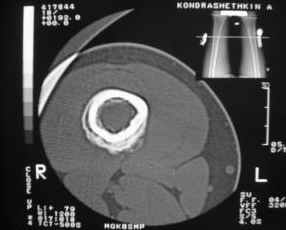

Здравствуйте, уважаемые коллеги!Представляю вашему вниманию интересный случай и пока что непонятный для меня в диагностическом плане. На днях в наше отделение (детской ортопедии и травматологии) поступил 13-летний мальчик по направлению из поликлиники с диагнозом: остеома нижней трети правого бедра.

Анамнез практически никакой: в следствие травмы (растяжение связок коленного сустава) от 07.11.2004 выполнены Rg-граммы в травмпункте и обнаружено опухолевидное образование. Первичные Rg-граммы я не публикую, так как они заметно худшего качества, да и динамики за прошедшие три недели не отражают. Болевой синдром купирован в течение трёх дней. В настоящий момент мальчика ничего не беспокоит. Ходьба не нарушена, опухоль пальпируется с трудом по задней поверхности в н\3 правого бедра, пальпация безболезненна, объем движений в суставах правой нижней конечности полный и симметричный. Кожа над опухолью не изменена.В нашей клинике проведено дополнительное обследование: общие анализы крови и мочи, биохимия крови без особенностей. Выполнены Rg-граммы на цифровом Siemens обычные и продольные томограммы срезами 3-5 мм, а также компьютерная томография поперечными срезами по 5 мм. Прошу обратить внимание, что на приведённых томограммах видны две полости 10х15 мм и 15х60 мм. Также имеются два опухолевидных образований наслаивающихся друг на друга: уплощённое и вытянутое 10х100 мм и элипсовидной формы 15х30 мм. Это хорошо заметно на фото a_1.jpg c_1.jpg и d_1.jpg. Плотность внутри полостей 125% от плотности костномозгового канала, плотность наружного опухолевидного образования 55% от плотности кортикального слоя. Также отмечается линия перелома по центру наружного опухолевидного образования.Исходя из полученных данных мнения в плане диагноза несколько разделились от 1)сочетания кортикальной фиброзной дисплазии и латентно протекавшего маршевого перелома н\3 правого бедра до 2)остеосаркомы. В отношении первого варианта не сходится отсутствие клиники при переломе такой крупной кости как бедро, второй вариант вообще оставлю без комментария, ибо некомпетентен. Хотелось бы услышать мнения коллег, с удовольствием ознакомлюсь с любыми предположениями и замечаниями.С уважением, Александр Е. КлоковОтделение детской ортопедии и травматологииБСМП г. Мурманска.